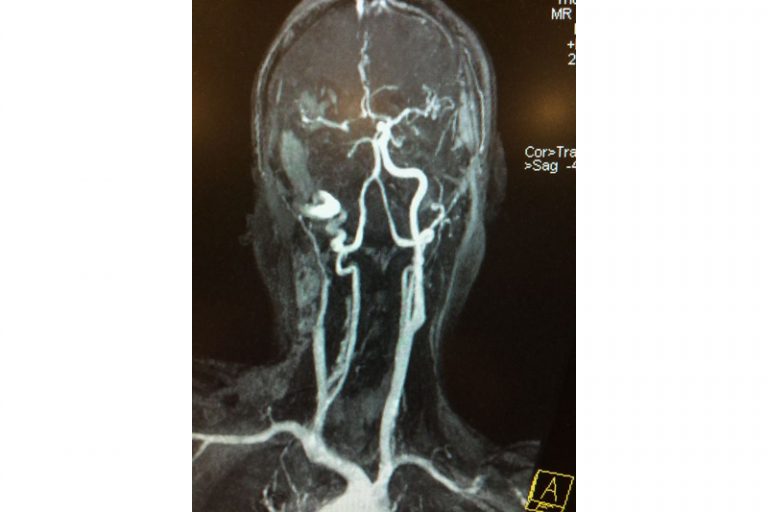

圖:磁力共震造影顯示羅先生右邊頸和腦部血管大動脈全部都被血栓堵塞著。

羅先生被送往私家醫院的第一步是進行緊急磁力共振造影,報告顯示羅先生右邊頸和腦部血管大動脈全部都被血栓堵塞着,右邊大腦缺血水腫,導致左邊手腳冇力和神智半昏迷。經過腦血管外科醫生的診斷和急救,在全身麻醉下,醫生使用尤如髪絲微細的導管,經過病人右邊大腿的腹股溝的大動脈而入,導管再經過腹部和胸腔的大動脈一直向上,遊走到病人右邊的頸和腦部血管大動脈,進行機械式血栓吸取內血管治療急救。